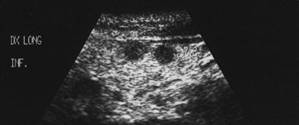

Lob drept , proiectie trasversala si longitudinala.

Femeie 19 ani. Leziune marcant hipoecogen cu intarire posterioara, de 16x20x26mm (4 cc) in lobul drept.

Examen citologic: macrofagi, fara tireocite.